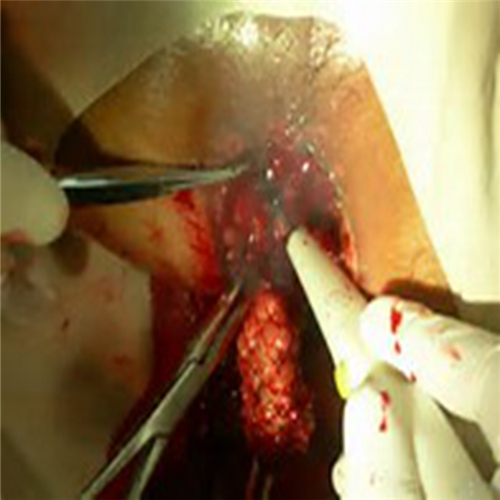

直腸息肉切除

直腸息肉手術過程

直腸息肉割除手術